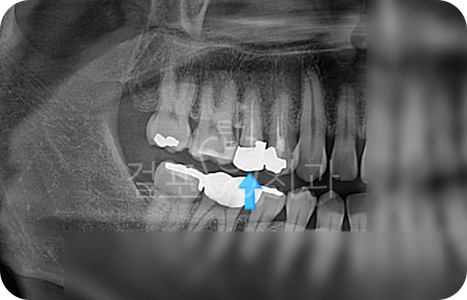

• 치아 파절로 내원하신 분입니다. 잇몸뼈가 튼튼하신 분으로 발치즉시 임플란트가 가능하였습니다.

Before

After

• 치아 뽑은 자리 잇몸염증이 매우 심한 상태였습니다. 잇몸상태가 좋지 않아도

발치 즉시 임플란트를 시도할 수 있습니다. 다만, 2~3달 지난 후 수술한다면 더 안전하므로 이런 경우 즉시 식립을 추천드리지 않습니다. 발치 몇 달 후 상악동 거상술과 뼈이식 임플란트를 함께하여 수술을 완료하였습니다.